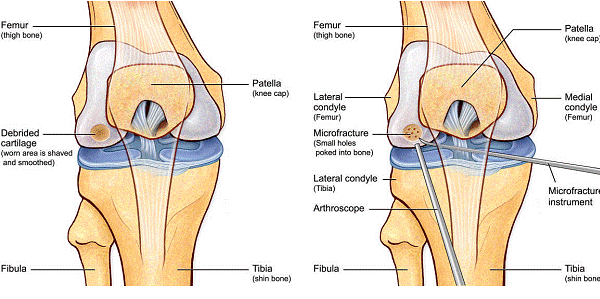

Chirurgul trebuie sa fie foarte atent atunci cand examineaza posteriorul condililor femurali. Daca se semnaleaza orice vatamare/rana/deteriorare pe suprafetele articulare, trebuie sa se cerceteze atent calitatea cartilagiului. Orice flapsuri instabile sunt inlaturate prin folosirea unui aparat de ras electric artroscopic sau curette. Apoi, un curette este folosit pentru a debrida stratul de cartilagiu calcifiat de la baza in toata grosimea defectului. Acest pas se bazeaza pe activitatea lui Frisbi, care a demonstrat vindecarea suprafetei articulare superioare la un cal, cand stratul cartilagiului calcifiat este indepartat. Cand indepartam stratul cartilagiului calcifiat, in general nu se foloseste un aparat de ras. Cu un aparat de ras este dificil de controlat cantitatea de os eliminat, si este posibil ca osul subcondral sa fie afectat.

Dupa indepartarea cu succes a stratului de cartilaj calcifiat, o andrea este folosita pentru a face mai multe gauri mici (mirofracturi) in osul expus al defectului condral aflate la distanta de 1-2 mm. Trebuie lasata o punte de oase potrivita intre gauri. Tehnica de microfracturi are numeroase avantaje fata de foraj. Mai intai de toate, creaza o leziune termala mai mica. Mai mult, cu microfracturi, chirurgul este capabil sa intre in zonele dificile ale suprafetei articulare cu un control mai bun asupra adancimii de patrundere. La finalizarea microfracturii, o suprafata aspra este generata pentru a aderenta cheagului de sange care contine celule mezenchimale nediferentiate de la osul subcondral. Trebuie avut grija ca cele mai marginase parti ale leziuni sa fie patrunse de andrea pentru a ajuta la vindecarea tesutului reparator la imprejmuirea suprafetei articulare. Odata ce microfractura este finalizata, pompa artroscopica este oprita pentru a se asigura ca sangerarea maduvei curge din gaurile mici umpland defectul.[54]

Fig.23. Diagrama microfracturi: a. Leziunea; b. Rezultatul interventiei.

Andrelele de microfracturare cu unghi reglabil actioneaza moderat astfel incat gaurile verticale pot fi facute fara daune termice. Se fac gauri chiar de la marginea defectului.

Fig.25.a. Debridarea. Fig.25.b. Microfracturare.